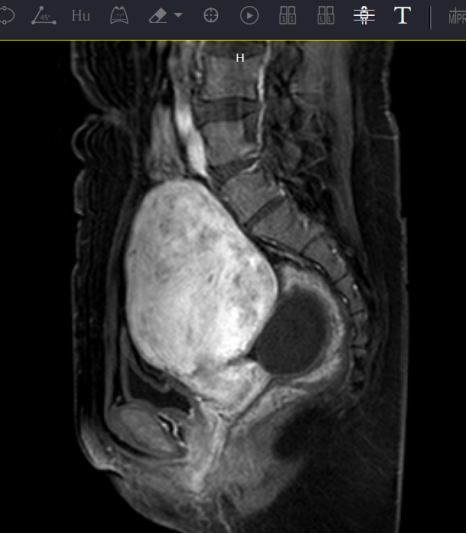

术前核磁影像

术后核磁影像显示消融范围